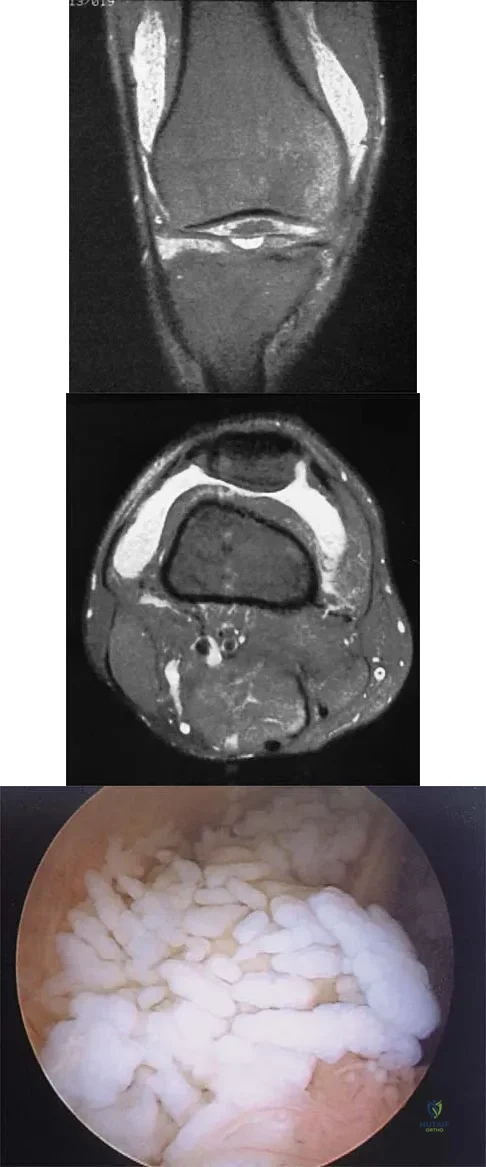

Question 55

A 30-year-old man who participates in recreational sports reports the spontaneous onset of intermittent pain and swelling about the right knee. Examination reveals a 3+ effusion, with a range of motion of 10 degrees to 60 degrees. He has mild diffuse tenderness but no instability. MRI scans and an arthroscopic view are shown in Figures 39a through 39c. Management should consist of

Explanation